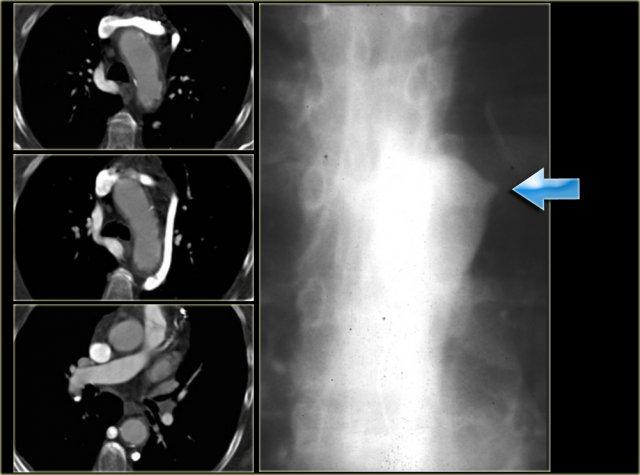

On the left a chest film of a young adult with a cough.

There is a right paratracheal mass.

The differential diagnosis is tumor, adenopathy or vessel (right arch, dilated azygos vein, dilated aberrant right subclavian artery).

On the left axial images and posterior view of volume rendered reconstruction.

Describe the findings and then continue.

The findings are:

- four vessel sign

- double arch

- right arch higher and larger

- esophagus and trachea are completely encircled

The narrowing of the trachea is seen on the axial images, but better appreciated on the MPR and Volume Rendered image.